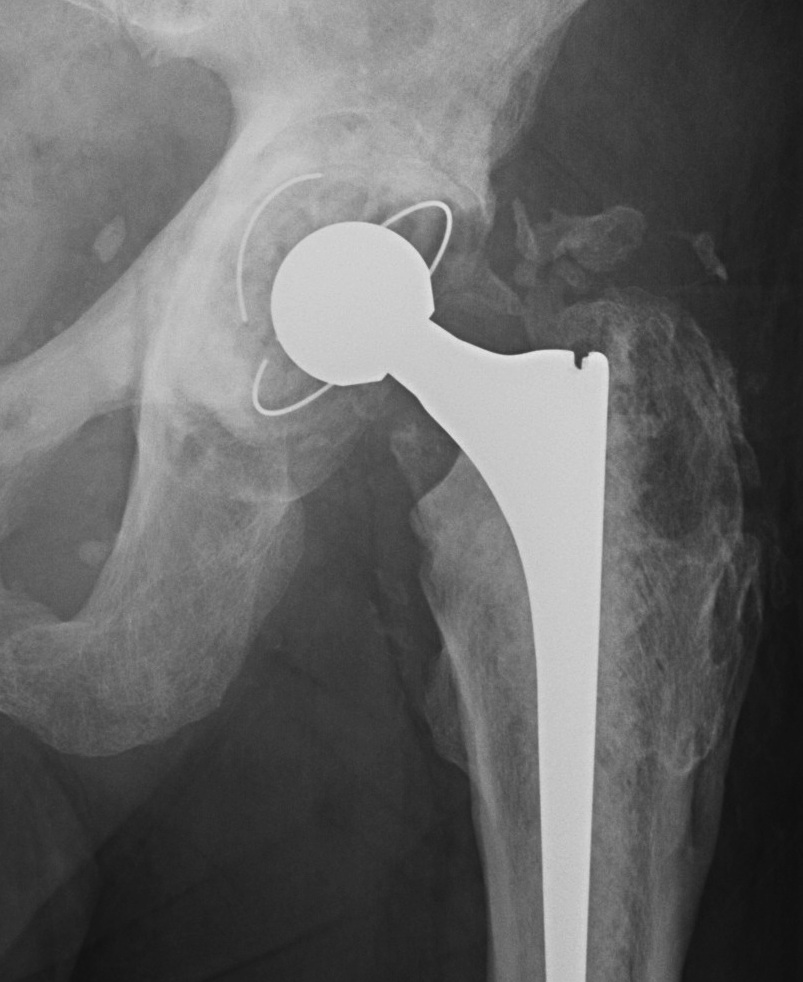

Brooker Classification: Type III and Type IV clinically relevant

Type I: Isolated islands of bone

Type II: Bony spurs from pelvis and proximal femur, gap > 1 cm

Type III: Gap < 1 cm

Type IV: Apparent ankylosis